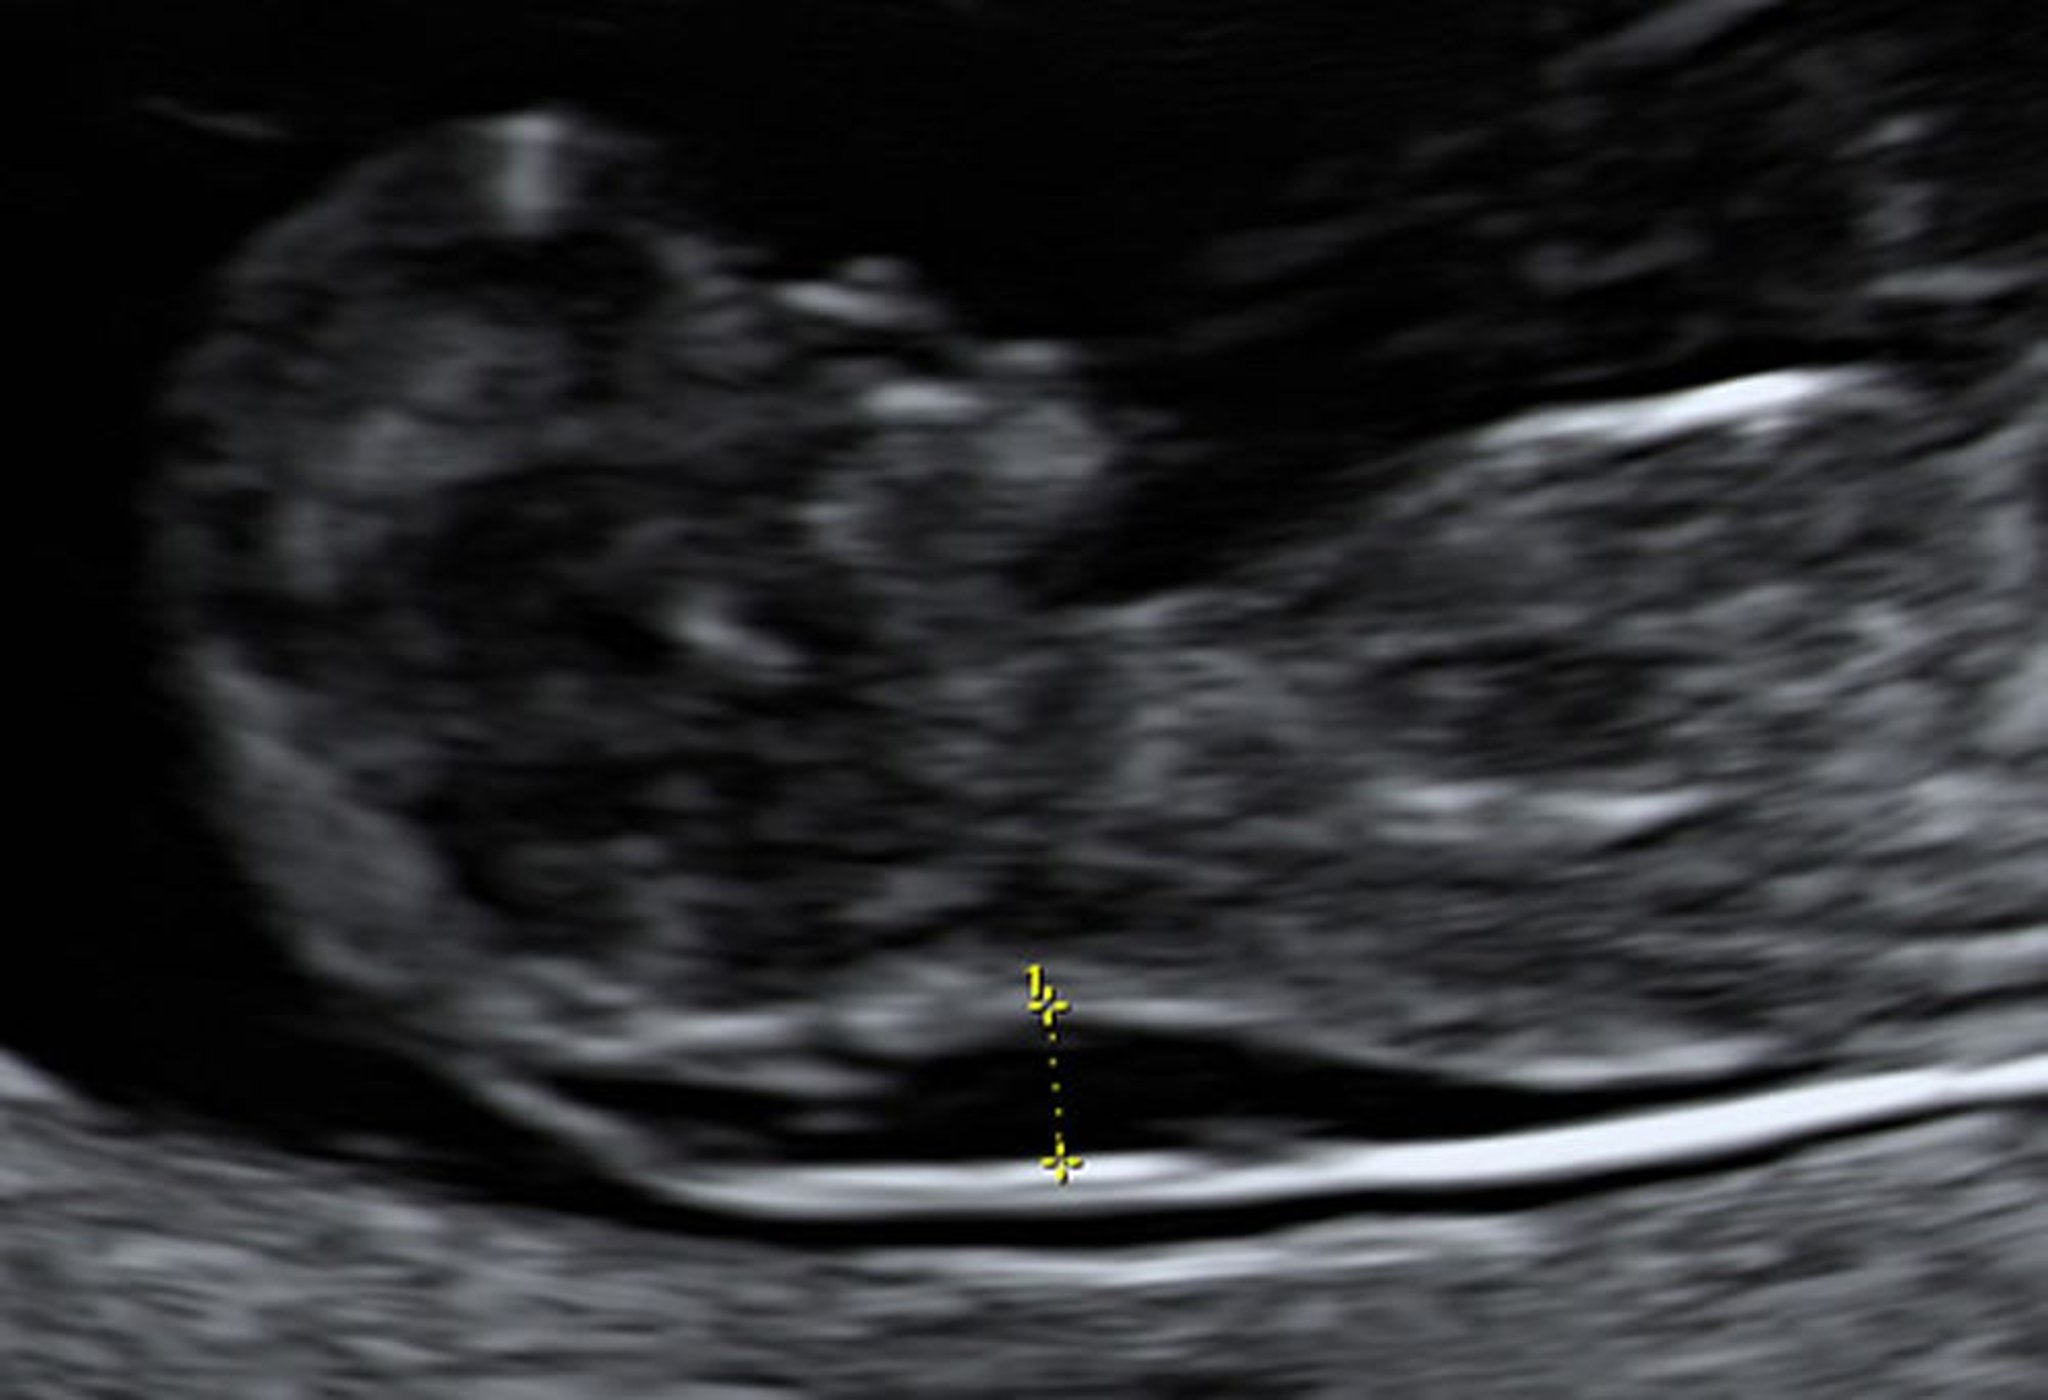

Ultrassonografia mostrando aumento da translucência nucal em um feto com 10 semanas

A biópsia da vilosidade coriônica indicou que esse feto tinha síndrome de Down.

Foto de Jeffrey S. Dungan, MD.